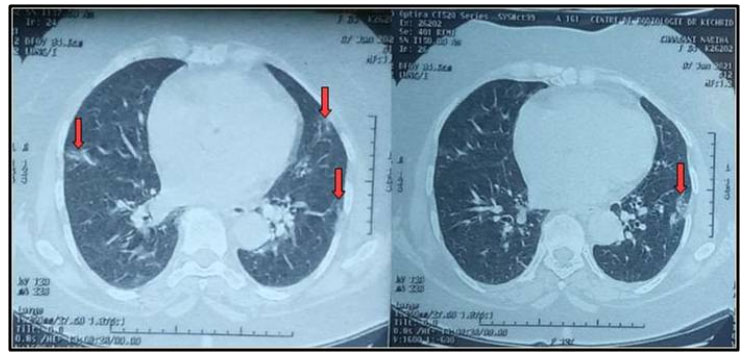

Figure 1: Non-contrast chest CT scan showing bilateral peripheral ground-glass opacities and crazy paving (red arrows) typical pattern of COVID-19 pulmonary infection (percentage of lung involvement at 10%).

A 65-year-old female patient with medical past history of obesity (body mass index (BMI) at 35 kg/m2), hypothyroidism treated by levothyroxine replacement therapy, was admitted in pulmonology department for confirmed COVID-19 pneumonia with two weeks history of fever, chills, asthenia, dry cough, and progressive shortness of breath, with initial non-contrast chest computed tomography scan (chest CT scan) showing bilateral peripheral ground-glass opacities and crazy paving with estimated percentage of lung involvement at 10% (Figure 1). She was managed initially with oxygen-therapy with nasal prongs associated to antibiotics, dexamethasone 6 mg/12 h, anticoagulation, hydration, and vitamins. On day four of admission, the patient developed a rapid onset of retrosternal chest pain associated to a moderate acute respiratory failure with severe hypoxemia: oxygen saturation (SpO2) of 88% under 15 L/min of oxygen with a non-rebreather mask. In front of the worsening of her state, she was transferred to our intensive care unit (ICU). Upon admission, her respiratory rate (RR) was of 35 breaths/min with struggle signs and hypoxemia and soft-tissue crepitus bilaterally. She was conscious with stable hemodynamic state. Laboratory tests revealed an elevated C-reactive protein (CRP) concentration of 53 mg/L (reference:<5 mg/L). Complete blood count showed a leukocytosis of 11.8×109/L (reference: 4–10×109/L), with lymphopenia (0.4×109/L). She had hepatic cytolysis with alanine aminotransferase (ALAT) and aspartate aminotransferase (ASAT) at 100 IU/L (reference:<45 IU/L) and 68 IU/L (reference: <50 IU/L) respectively. Serum level of D-dimer was at 457 µg/L (reference:< 500 µg/L). Arterial blood gas (ABG) showed a pH:7.41, PaCO2:43 mmHg, PaO2:74 mmHg, HCO3:27 mmol/L and PaO2/FiO2 ratio at 205. A contrast-enhanced chest CT scan was performed showing diffuse lower neck subcutaneous emphysema associated with diffuse PM and diffuse bilateral ground-glass opacities with posterior and peripheral predominance associated to alveolar consolidation with estimated percentage of lung involvement at 90% consistent with critical COVID-19 pneumonia (Figure 2A, Figure 2B, Figure 2C, Figure 2D). Urgent mediastinal decompression with chest drainage tube wasn’t immediately indicated in front of the maintained stable hemodynamic state, so we decided the conservative therapy with reduced airway pressure with non-invasive ventilation (NIV) [pressure support (PS) of 12–14 cmH2O, positive end expiratory pressure (PEEP) of 4 cmH2O, and fractional inspired oxygen (FiO2) of 100%]; awake prone positioning and close monitoring. Initially we obtained a slight improvement of his respiratory state. At day 7 of ICU stay she was intubated in front of NIV failure. The patient was ventilated with protective ventilation with volume assist-control ventilation mode (VAC mode) [tidal volume (Vt) at 6 mL/kg predicted body weight (PBW), PEEP at 4 cmH2O: low level in front of the PM, respiratory rate at 30 breaths/min and 100% of FiO2. She was immediately put under continuous infusion of sedation and neuromuscular blockers. Despite protective ventilation with lower pressure, there was a maintained severe hypoxemia, and the patient passed away due to refractory hypoxemia few hours later.